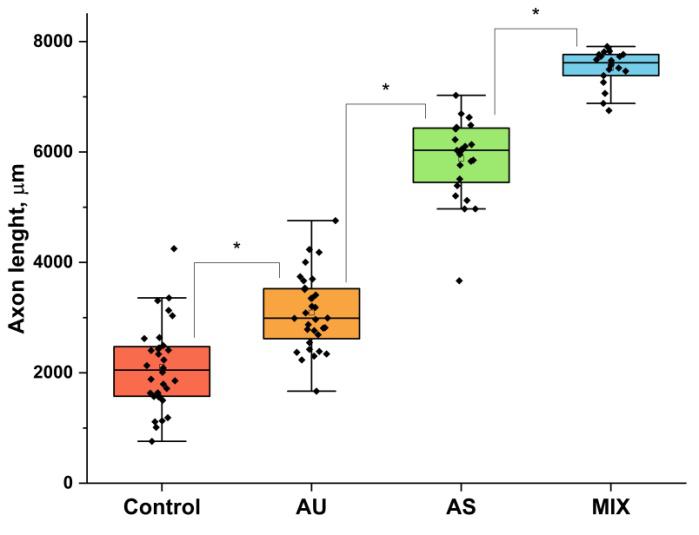

Дорзальный корешковый ганглий культивированный на предзасеянных швановскими клетками композитных волокнистых подложках

Дорзальный корешковый ганглий культивированный на предзасеянных швановскими клетками композитных волокнистых подложках

Наилучшие результаты продемонстрировали скаффолды из композитного двухслойного наноматериала, состоящего из слоёв волокон с диаметрами 60 нм и 200 нм. Подложки из такого материала с предварительно выращенными ШК при контакте с органоидами спинного мозга (дорзальными корешковыми ганглиями) значительно ускоряют рост аксонов спинномозговых нервов в модели ex vivo».

Композитный материал покрытий ШК обеспечивает наибольшую скорость роста нервных отростков. AU — ультратонкие волокна со средним диаметром 60 нм, AS — субмикронные волокна со средним диаметром 200 нм. MIX — композитный материал из 60 нм и 200 нм волокон

Композитный материал покрытий ШК обеспечивает наибольшую скорость роста нервных отростков. AU — ультратонкие волокна со средним диаметром 60 нм, AS — субмикронные волокна со средним диаметром 200 нм. MIX — композитный материал из 60 нм и 200 нм волокон